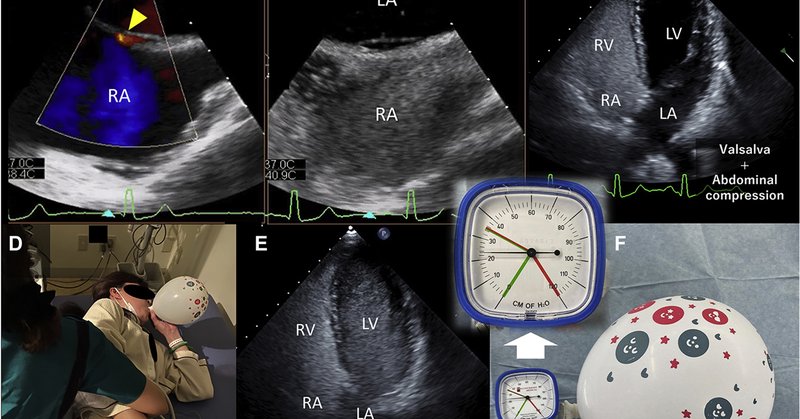

Excited to announce that my new provocative maneuver to detect PFO using party balloon during Saline Contrast Transthoracic Echocardiography has been published in JACC: Case Reports. https://t.co/iUdmGljWHF